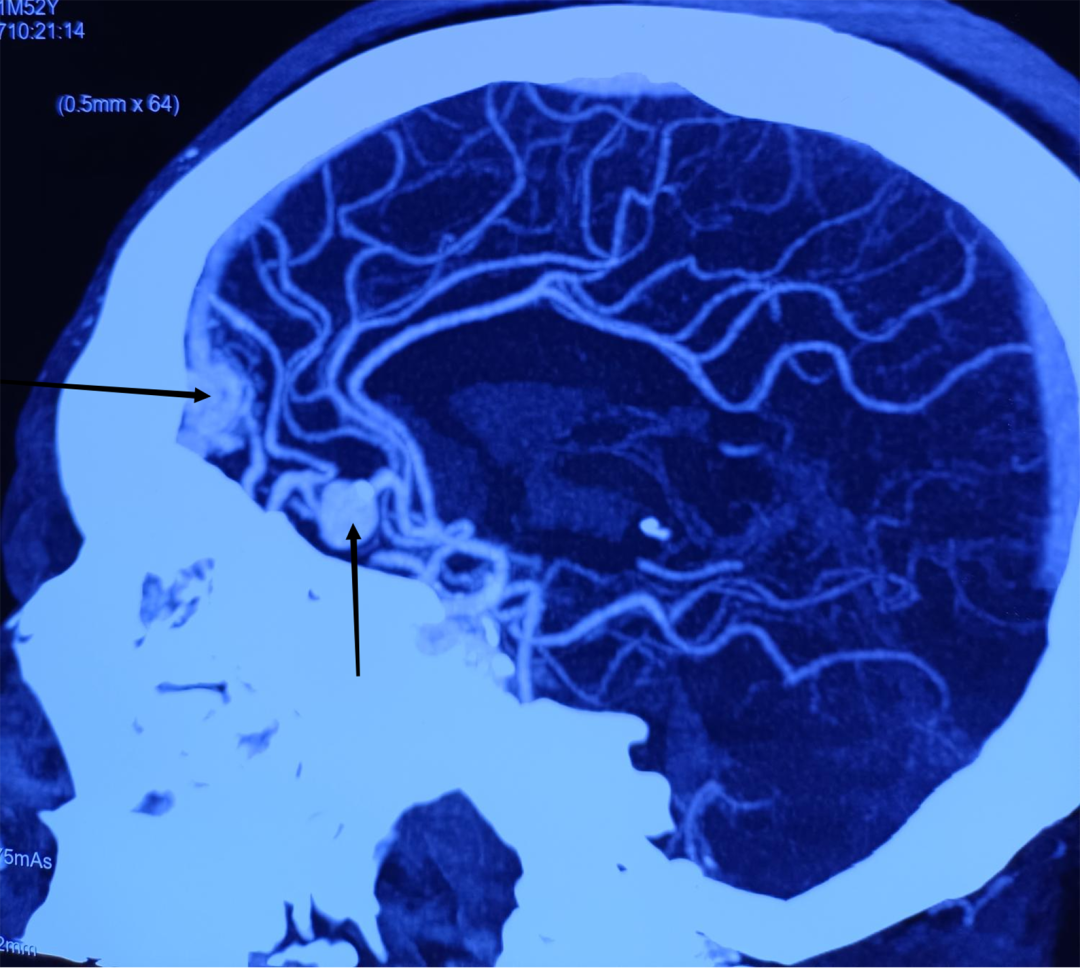

2022年10月27日,神经外科收住了一位“动脉瘤破裂出血”的危重患者。宫某入院时头痛、头晕、烦躁、意识模糊,双下肢无力。田垒医生接诊后立即给患者完善检查,立即向二线医师汇报患者情况。董永军副主任为患者查体,仔细查看头颈CTA和颅脑CT,在北医三院神经外科驻延专家张嘉教授和田德洲主任的指导下,对患者的身体状况进行了综合评估,考虑为脑动脉瘤合并动静脉畸形。面对如此凶险的病情,必须准确而快速地进行治疗。时间就是生命,决定立即为宫某实施全脑血管造影术+左侧大脑前动脉A2段动脉瘤介入栓塞术,防止动脉瘤二次破裂。

在介入科和麻醉手术科医护人员的全力配合下,董永军副主任给患者做了全脑血管造影,确定了动脉瘤的大小和位置,然后输送释放弹簧圈,顺利栓塞破裂出血的动脉瘤,经过2小时的“奋战”,手术顺利完成。考虑到患术前意识不清及脑血管疾病的潜在风险,转入重症监护室观察治疗。术后第二天患者清醒,言语、四肢活动基本正常,转入普通病房行腰大池引流。术后第三天患者再次意识不清、烦躁,复查颅脑CT显示:急性梗阻性脑积水,急诊行侧脑室穿刺引流术,手术历经20分钟,手术顺利。二次术后第二天,患者意识清楚,言语、运动功能正常、饮食均可。术后第6天,患者开始尿量增加,淡漠。尿量达7000ml每天,血钠降至112mmol/L。结合化验结果及临床表现,考虑发生了尿崩症。给与补充电解质,口服去氨加压素片、双克等治疗后尿量逐渐恢复正常,电解质也随之恢复正常。现患者症状基本消失,顺利出院。